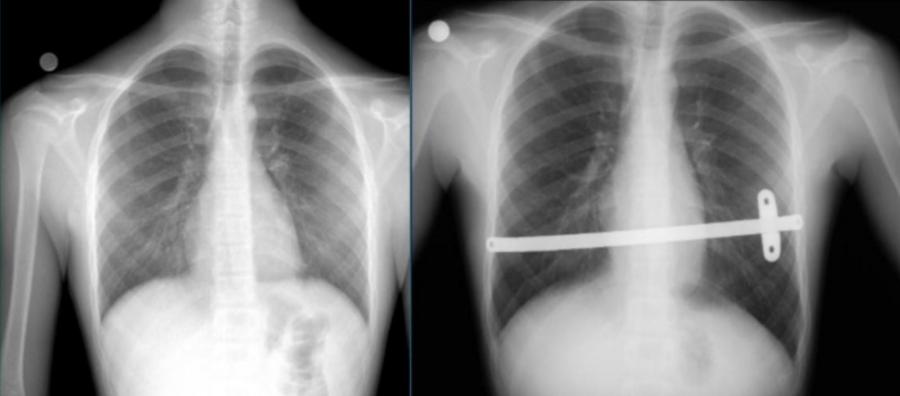

Röntgen: Kunduracı göğsü derecesinin belirlenmesi ve muhtemel ek problemleri görüntüleme amacıyla röntgen çekmekte fayda vardır.

Kunduracı göğsü tedavisinde günümüzde Nuss yöntemi dediğimiz kapalı kamera yardımı ile çökük olan kısmın altından çelik veya titanyumdan üretilmiş bar denilen malzemenin konulması ile yapılır.

Nuss yöntemi, kamera eşliğinde kapalı olarak yapılan minimal invaziv ameliyat tekniğidir. Bu yöntemin daha kısa ameliyat süresi, estetik küçük ameliyat izleri, daha kısa hastanede kalış süresi ve ameliyat sonrası yüksek hasta konforu gibi avantajları bulunmaktadır.